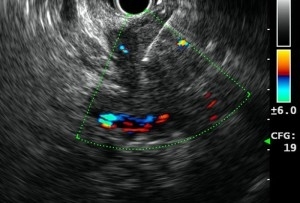

胰臟是一個位於胃部背較後位置的器官,主要提供協助消化的酶素及調節新陳代謝的荷爾蒙。根據醫管局香港癌症資料統計中心於2015的數字,胰臟癌雖然不是香港十大常見癌症,但卻高踞香港十大死亡癌症的第四位,而其死亡率排名於第四的原因,很大機會是由於早期胰臟癌通常並無明顯症狀,並加上其位置相對較隱蔽,因而較難被發現。當有明顯症狀時,疾病多為較後期或不能以手術作治療的階段,即使能進行手術進行切除,其存活的時間一般較其他癌症病患者短。胰臟癌的症狀可包括黃疸,糞便顏色變淡,尿色變深,腹痛或背痛,不明原因體重下降及無飢餓感。 市民若要檢查有否患上胰臟癌,本中心亦有提供以下檢查作出診斷︰

- 內視鏡超聲波檢查

- 內視鏡超聲波導引幼針穿刺檢查